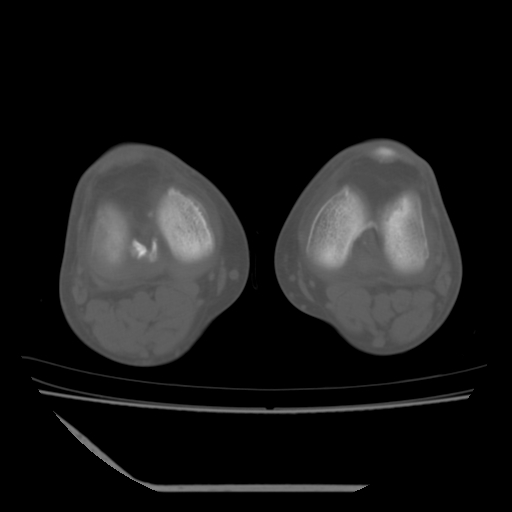

标题: CT13225:老年男性,左膝关节疼痛数月;请各位老师讨论。 [打印本页]

标题: CT13225:老年男性,左膝关节疼痛数月;请各位老师讨论。

骨质增生,骨性关节面硬化,关节积液,考虑退行性骨关节病

关节腔内少量积液,关节面退变。

双膝退变

骨质增生,骨性关节面硬化,关节间隙失常,关节积液,考虑退行性骨关节病.

骨质增生,骨性关节面硬化,关节积液,考虑退行性骨关节病。

这个病例诊断:退行性骨关节炎